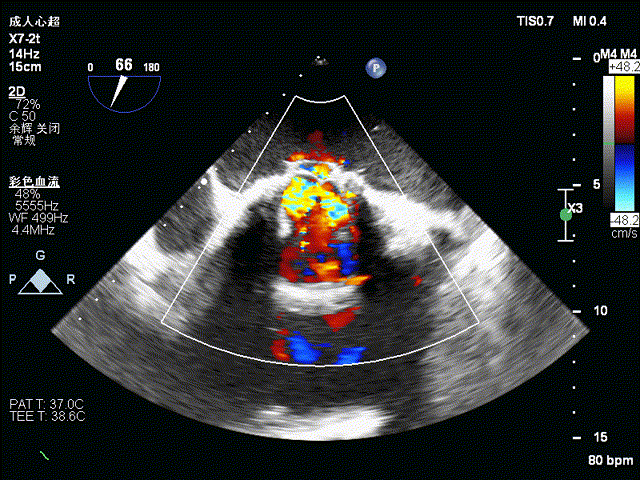

术前食道超声示:

术前食道超声